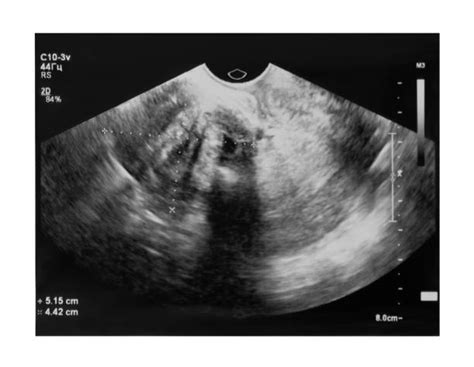

Molárne tehotenstvo (Mola hydatidosa) sa typicky prejavuje v druhom trimestri tehotenstva krvácaním, bolesťami v panvovej oblasti a nadmerným vracaním. Na to, že niečo nie je v poriadku, vás upozornia rôzne symptómy - vaginálne špinenie alebo krvácanie, nevoľnosť, vracanie, prípadne bolesti brucha. Pri návšteve v poradni gynekológ zistí nápadne rýchly rast maternice, ktorá veľkosťou nezodpovedá štádiu tehotenstva. „To je hlavným príznakom moly. Ďalším je nepravidelné krvácanie. V krvi, ktorá vyteká z hrdla maternice, môžeme nájsť drobné cystičky - moly. Ultrazvukový obraz je známy odrazmi mnohopočetných priehradok moly pod názvom „snežná búrka“, ktoré na monitore naozaj vyzerajú ako husté sneženie. Typické pre toto ochorenie je tiež zobrazenie mnohopočetných luteinných cýst na vaječníkoch,“ vymenúva gynekologička celý rad príznakov.

- Ultrazvukové vyšetrenie: Pomocou tohto vyšetrenia sa odhalí abnormálny typ maternice, a chýbanie plodu. Ultrazvukový obraz je známy odrazmi mnohopočetných priehradok moly pod názvom „snežná búrka“, ktoré na monitore naozaj vyzerajú ako husté sneženie. Typické pre toto ochorenie je tiež zobrazenie mnohopočetných luteinných cýst na vaječníkoch.

Kompletná mola sa vyskytuje v 1 z 3000 - 4000 tehotných. Vzniká oplodnením prázdneho vajíčka, jednou alebo dvomi spermiami, ktoré sa rozdelia a obsahuje iba otcovské chromozómy 46 XX, ďalej sa nevyvíja. Ultrazvukovým vyšetrením nenájdeme plod, ale obraz tzv. sneženia. Je potrebné ukončiť tehotenstvo tzv. vyčistením dutiny maternice s následným sledovaním hladín HCG- 1x týždenne do negativity a následne 1x mesačne do jedného roka. Ďalšie tehotenstvo sa odporúča minimálne rok po negatívnych hodnotách HCG.